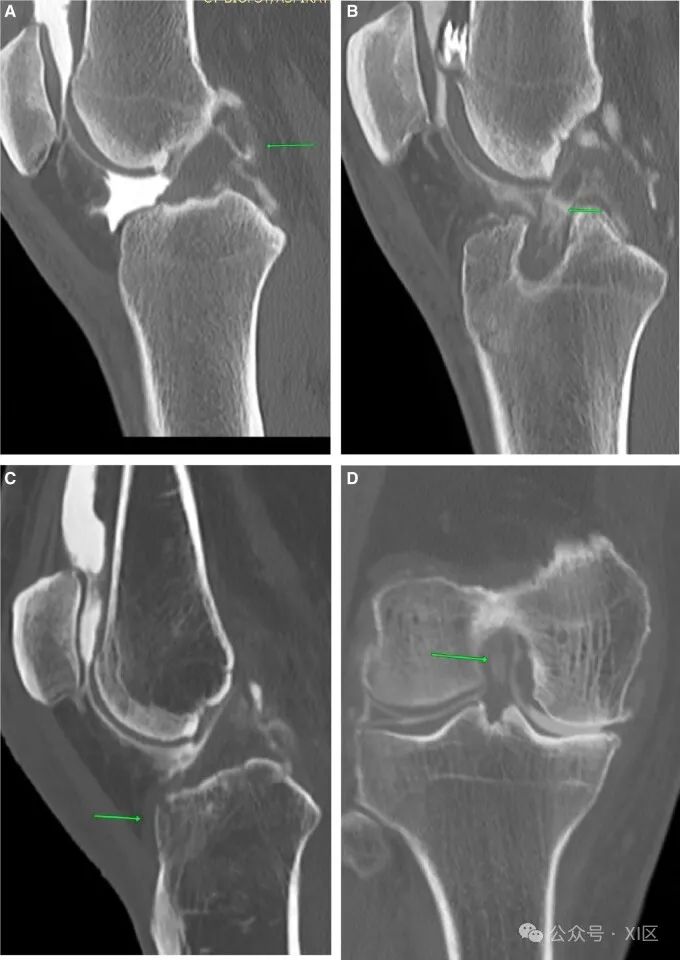

前交叉韧带(ACL)撕裂是导致内部损伤的最常见原因。如果仔细观察,预先计划的CT显示股骨外侧髁的血肿和压痕(图1)。在手术台上评估过程中可以看到带血迹的抽吸物,对比后图像显示全厚度缺损。仔细检查横断位图像至关重要,因为微小的全厚度撕裂很容易被忽视。CT关节造影提供了一个独特的优势,因为与MRI不同,多平面重建(MPR)可以在任何平面上进行,而无需增加扫描时间。CT对ACL重建膝关节特别有益(图1B),因为金属制品的原因,MRI是禁忌。必须仔细检查软组织窗图像,以便更好地解释。ACL撕脱伤通常是潜在骨折的副产品。预规划图像显示了发际骨折(图1C)。台上评估显示吸出物带血,对比后图像显示ACL和骨折线增厚。在CT关节造影检查中很难检测到部分撕裂或粘液样变性。在适当的临床环境中,前交叉韧带的体积外观、纤维的广泛分离和物质内对比可以增加诊断的可信度(图1D)。

图1 ACL撕裂:(A)关节造影后矢状位图像显示完全的ACL撕裂(箭头)。(B) 重建的前交叉韧带完全撕裂,(C)前交叉韧带撕脱(箭头)。(D) 物质内对比的粘液样变性(箭头)。后交叉韧带(PCL)损伤在外观上与ACL损伤非常相似(图2A)。PCL撕脱也与潜在的骨折和血肿有关(图2B)。